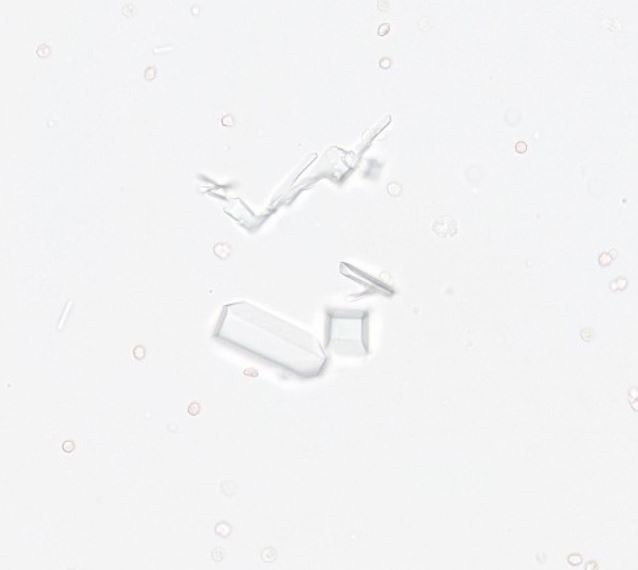

- Esame urine: globuli bianchi, globuli rossi, cristalli. L’analisi basata sull’intelligenza artificiale con un’elevata precisione delle prestazioni paragonabile a quella di un patologo clinico guida la diagnosi e la selezione del trattamento. La preparazione rapida e semplice dei vetrini con risultati coerenti consente di completare i test e fornire informazioni diagnostiche in un’unica visita. Parte di una suite connessa di strumenti diagnostici per l’analisi delle urine, AI Urine Sediment massimizza la capacità diagnostica in modo da poter fornire un’assistenza continua con meno ritardi a un maggior numero di pazienti.

- Identifica globuli rossi, globuli bianchi, cellule epiteliali, cristalli di struvite e ossalato di calcio diidrato, calchi ialini e non ialini e cocchi e bastoncelli